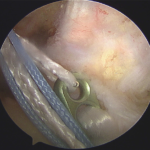

Reconstruction involves placing a graft inside the knee by arthroscopic surgery (keyhole). A

>90% success rate is normal with some deterioration over time depending upon other damage within the joint.

In the surgery a graft will be harvested to use to reconstruct the torn ligament. Usually two of the hamstring tendons are taken, but sometimes other suitable graft choices are used. This will be discussed with you prior to the operation. The remnants of the torn ACL are removed with keyhole surgery and tunnels are made in the tibia (shin bone) and femur (thigh bone) to allow the graft to be positioned across the knee. The new reconstructed ligament is then fixed at both ends to secure it in place.

Femoral fixation – Superior fixation of the graft in the femoral tunnel is done with an all-inside technique using Endobutton (smith-nephew usa).